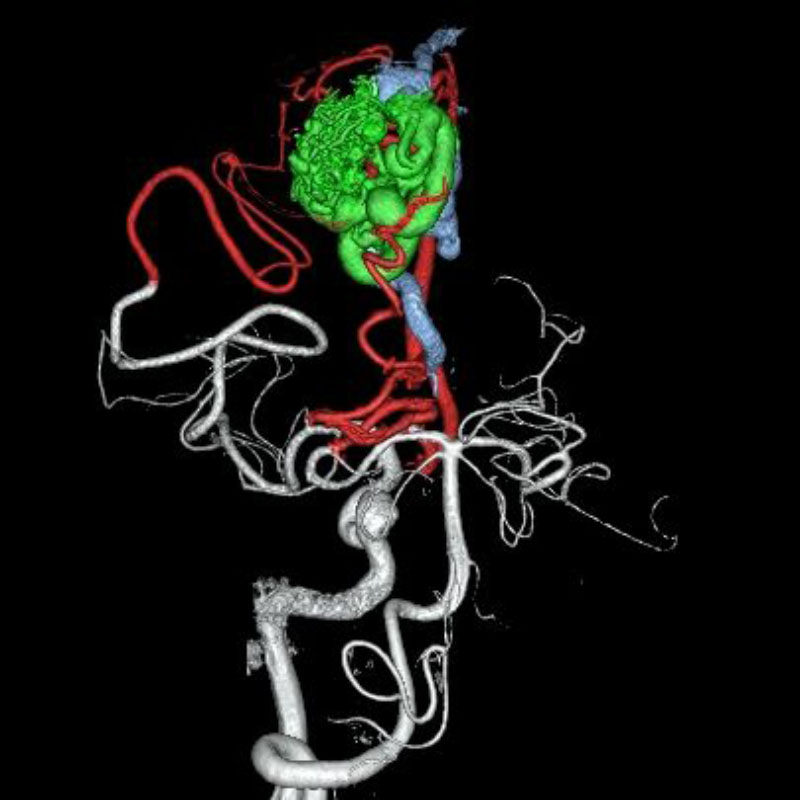

脳動静脈奇形

血管塞栓術

松田/濵田/元永